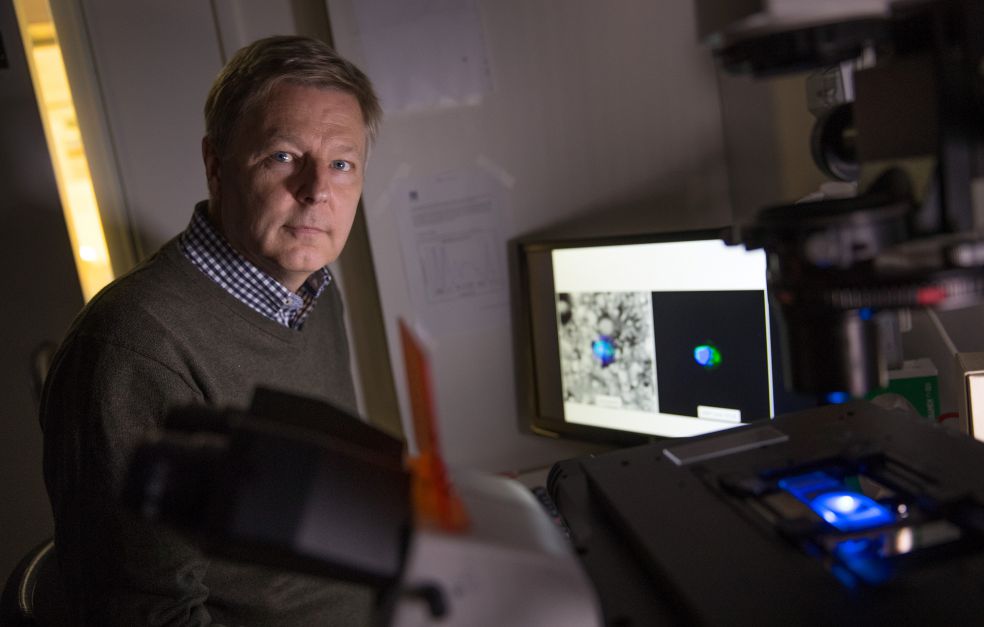

Det är tack vare optiska fibrer som vi kan surfa på internet och skicka stora datamängder i höga hastigheter härs och tvärs runt jordklotet. I de fiberoptiska kablarna används ljuspartiklar, fotoner, för att överföra information, förklarar Fredrik Laurell som är professor i laserfysik på KTH. Normalt sett håller han till i Albanova, men är nu på besök på SciLifeLab i Solna för att träffa några kollegor som uppfinner medicinska applikationer.

Optiska fibrer och lasrar kan till exempel även användas för att studera celler och bakterier in vivo, i sin naturliga miljö. Fredrik Laurell leder ett femårigt projekt om multifunktionella fibrer som har stöd från Knut och Alice Wallenbergs Stiftelse. I projektet samarbetar han med en rad forskare som har olika specialiteter inom området optisk fysik.

Fredrik Laurell arbetar sedan många år med forskare vid RISE Acreo, som tidigare hette Institutet för optisk forskning. Hans viktigaste samarbetspartner där är Walter Margulis, som även är gästprofessor på KTH, och som också ingår i projektet om multifunktionella fibrer.

I labbet på SciLifeLab demonstrerar Fredrik Laurell en mini-flödescytometer, som med flourescens och fiberoptik kan identifiera och räkna specifika partiklar i en flödande vätska. Traditionella flödescytometrar är mycket större, det här är en förenklad och miniatyriserad variant av tekniken.